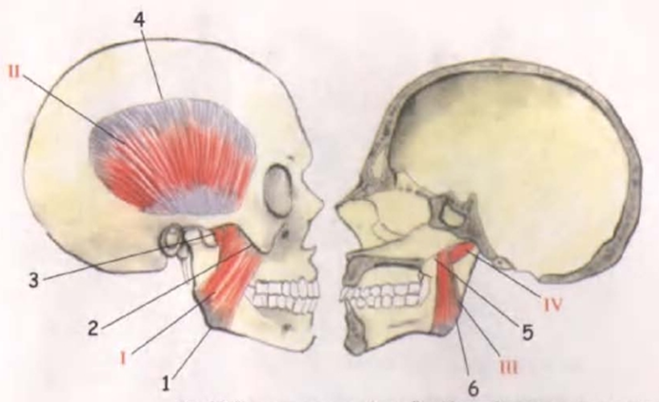

Анатомические изображения срединной сагиттальной линии черепа